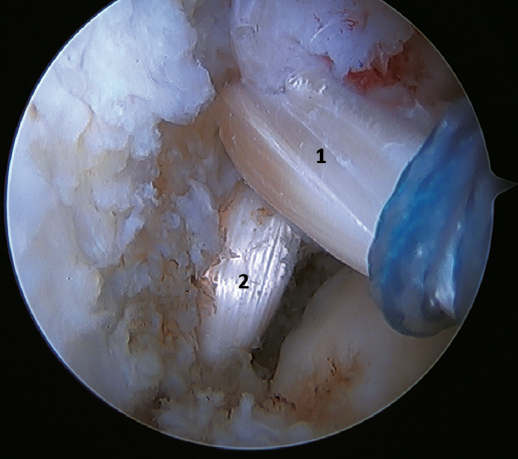

Un reciente consenso(64) recomienda la reconstrucción del LTFA y el LCF (Figuras 5 y 6) en aquellos casos de laxitud generalizada o cuando existe una mala calidad tisular. Otras indicaciones serían cuando existen dudas de la estabilidad subtalar o en aquellos pacientes con rotura del LCF. Para algunos autores, el IMC superior a 30 kg/m2 también sería una indicación para esta técnica.

Figura 5. Rotura del ligamento talofibular anterior y del ligamento calcaneofibular con mala calidad tisular del remanente ligamentoso.

Figura 6. Imagen artroscópica de una doble reconstrucción con aloinjerto del ligamento talofibular anterior (1) y del ligamento calcaneofibular (2), objetivándose la correcta tensión y posicionamiento de los fascículos.